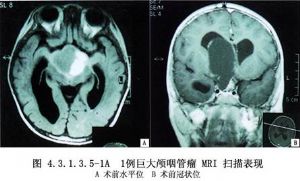

2.极少数始发于鞍上池的颅咽管瘤突破第三脑室底部或终板,进入第三脑室,且有时进入侧脑室,形成一个很大的脑室内瘤块。多见于较大儿童或成人,且实质性瘤块较囊性者更多,这种肿瘤虽可经额下入路手术,但对于其脑室内瘤块巨大者则需采用经脑室入路。

2.肿瘤显露 经胼胝体或经额叶皮质进入侧脑室后,沿脉络丛和丘纹静脉向前达室间孔,可见第三脑室内紫褐色肿物,有时该瘤通过室间孔突入侧脑室,可为囊性,或有钙化的实质性瘤块。

3.肿瘤切除 经室间孔显露肿瘤后,注意分辨其后下方的丘纹静脉由此穿入室间孔,与大脑内静脉相连,其上被覆侧脑室脉络丛(图4.3.1.3.4-2,4.3.1.3.4-3)。如肿瘤较小,室间孔未扩大,可于其前方切开一侧穹隆柱;如肿瘤较大,也可采用经脉络膜裂入路。肿瘤较软可被吸引器推动者,可于穿刺吸除囊液后,囊壁塌陷,再将其分块切除。CUSA是最理想的肿瘤切除工具,它不需要较大的暴露空间,还可用CO2激光切除囊内实质性瘤块,直至瘤壁变薄与脑室壁分开时为止。瘤壁向内推移,分离其与第三脑室的界面,用小棉片铺垫在肿瘤与脑室壁之间,使肿瘤向中央移动而脑室壁不为手术器械所伤。这样对于小的囊性颅咽管瘤且与脑室壁粘连不多者,可达到完全切除。

巨型第三脑室内颅咽管瘤常侵及脑室外结构,如视神经、视交叉、颈内动脉等,肿瘤基底常与周围结构粘连固定。从脑室内切除肿瘤时,需结合术前CT、MRI等影像检查资料与术中所见进行操作,要特别注意Willis动脉环前部发出的肿瘤供应血管,有时还有基底动脉系统发出的分支。肿瘤本身无血管,切除时出血不多,但与上述血管很难分离。如肿瘤较大且为实质性,周围粘连较紧,甚难完全切除,可行囊内及囊壁部分切除,打通室间孔,使脑积水好转,或者于瘤腔内置Ommaya贮液囊,以便日后肿瘤复发时经其穿刺抽吸囊液,亦可经其注入药物或核素。肿瘤切除后要注意脑脊液流通的情况,如室间孔开放不满意可切开透明隔,或行脑室-小脑延髓池或脑室-腹腔分流术,以解除梗阻性脑积水。